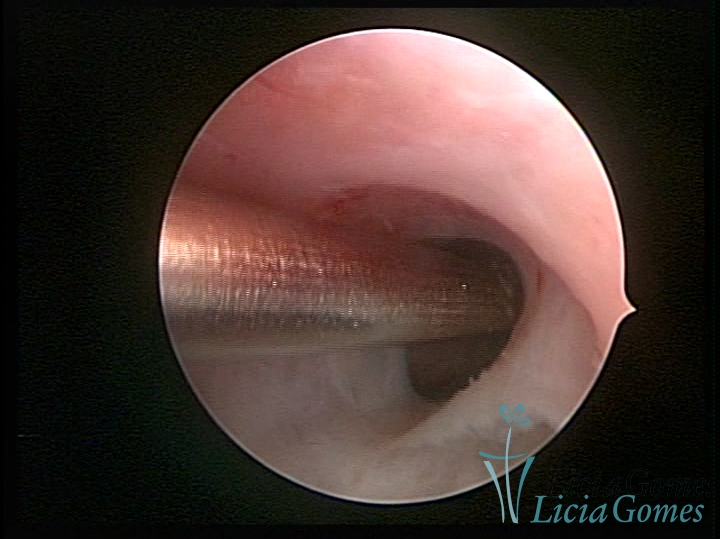

• SINÉQUIA TIPO FIBROMUSCULAR